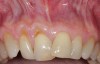

Fig 10. Cross-sectional view of the preoperative and postoperative (2 years). A three-dimensional increase of zone of keratinized and attached tissue is observed, restoring the lost attachment apparatus and correcting the gingival deformity in height and width.

Figure 10

Fig 11. Cross-sectional view of the preoperative and postoperative (2 years). A three-dimensional increase of zone of keratinized and attached tissue is observed, restoring the lost attachment apparatus and correcting the gingival deformity in height and width.

FIgure 11